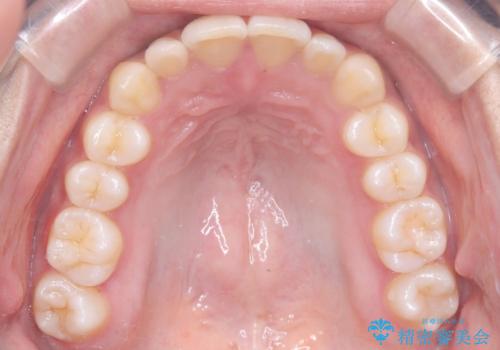

反対咬合と前歯のガタガタを非抜歯で改善

- 患者様は、上下の前歯のガタガタと反対咬合(下の歯が上の歯より前に出ている状態)を主訴として来院されました。診断の結果、抜歯を行わずに治療を進めるため、臼歯を遠心移動させてスペースを作り、IPR(インタープロキシマルリダクション)で歯間を調整する治療計画を立てました。インビザラインを使用して、透明で目立たない矯正装置により、歯列を整えながら噛み合わせも改善することを目標としました。

非抜歯での治療では、限られたスペースの中で効率的に歯を動かす必要があります。本症例では、臼歯を後方に移動させる遠心移動を行い、歯列のガタガタを改善しました。また、IPRを適切に行うことでスペースを確保し、歯根や歯肉への負担を最小限に抑えながら治療を進めました。インビザラインを使用することで、治療中も目立ちにくく、患者様の日常生活への影響を軽減しました。結果として、抜歯を行わずに美しい歯並びと自然な噛み合わせを実現し、患者様には大変満足していただけました。